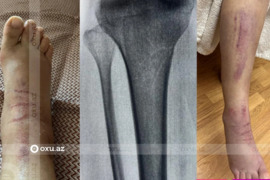

19 yaşlı oğlanı aldadaraq sinə böyütmə əməliyyatı ETDİLƏR- FOTOLAR

Çinin Uhan şəhərində 19 yaşlı oğlanı aldadaraq sinə böyütmə əməliyyatı ediblər. xarici mənbəyə istinadən xəbər verir ki, 19 yaşlı uşağa canlı yayımda çıxaraq çoxlu pul qazanacağına dair vədlər verilib. Gəncin anası bildirib ki, oğlu iyulun 28-də ora işə düzəlmək üçün gedən zaman yerli klinika işçilərini